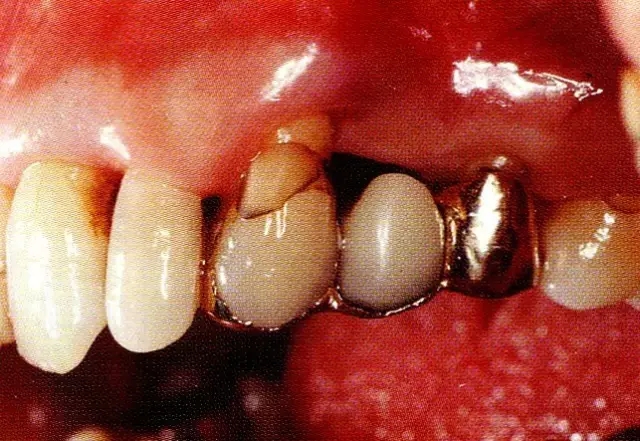

病例5  針對(duì)左右對(duì)稱性骨缺損,一側(cè)進(jìn)行非吸收性膜,另一側(cè)進(jìn)行吸收性膜處理的病例。

▲圖9-1  58歲,女性。右上2的上頜顎側(cè)可觀察到較大的3壁性骨缺損,術(shù)前牙周探診值時(shí)10mm。

640.webp (17).jpg